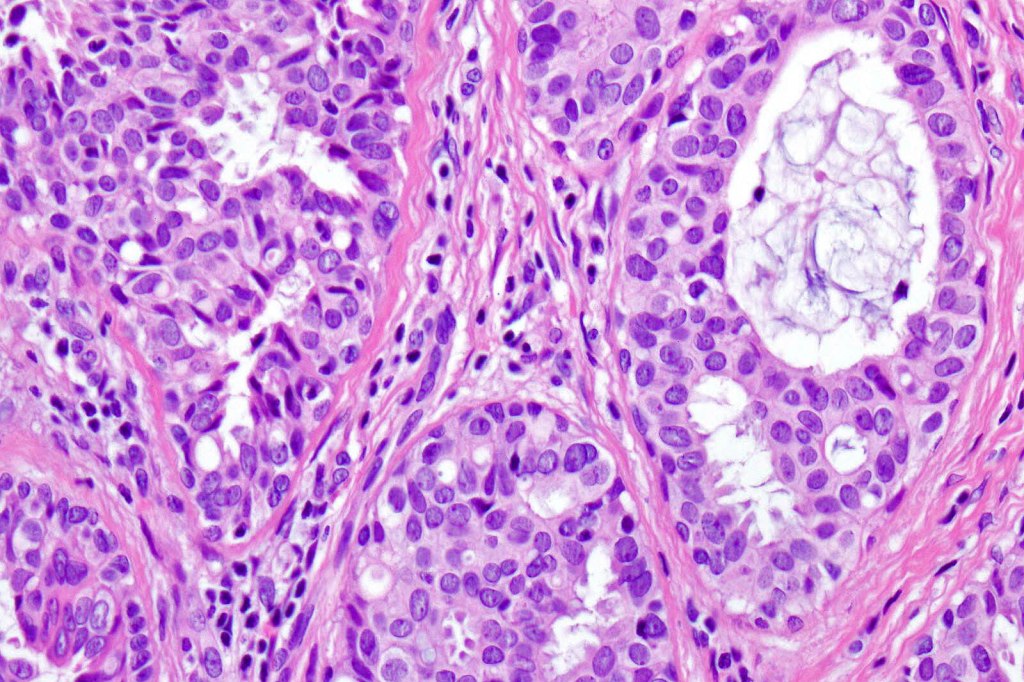

•Eosinophilic cytoplasm & small vesicular nuclei

•Mitoses scanty to absent

•No significant pleomorphism

•EMPSGCa– multiple nodules of uniform epithelial cells with vesicular nuclei & small nucleoli

•Few mitoses

•No abnormal mitoses